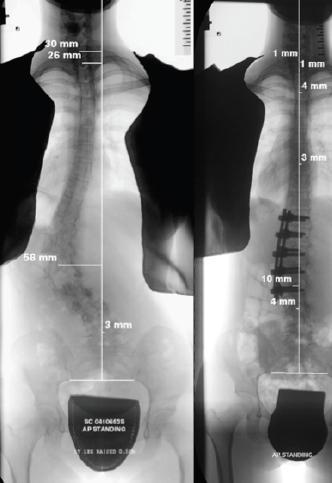

Surgery: (Figs. 8-10) For the very small number of children with severe curves, internal fixation is applied to the spine to correct the curve within the limits of safety. Surgery for scoliosis has been made very safe by major advances in surgical techniques including surgical navigation and the use of intraoperative spinal cord monitoring [1,6,7,8].

![]() Fig. 10 Anterior Spinal Fusion for correction of left thoraco-lumbar curve. |